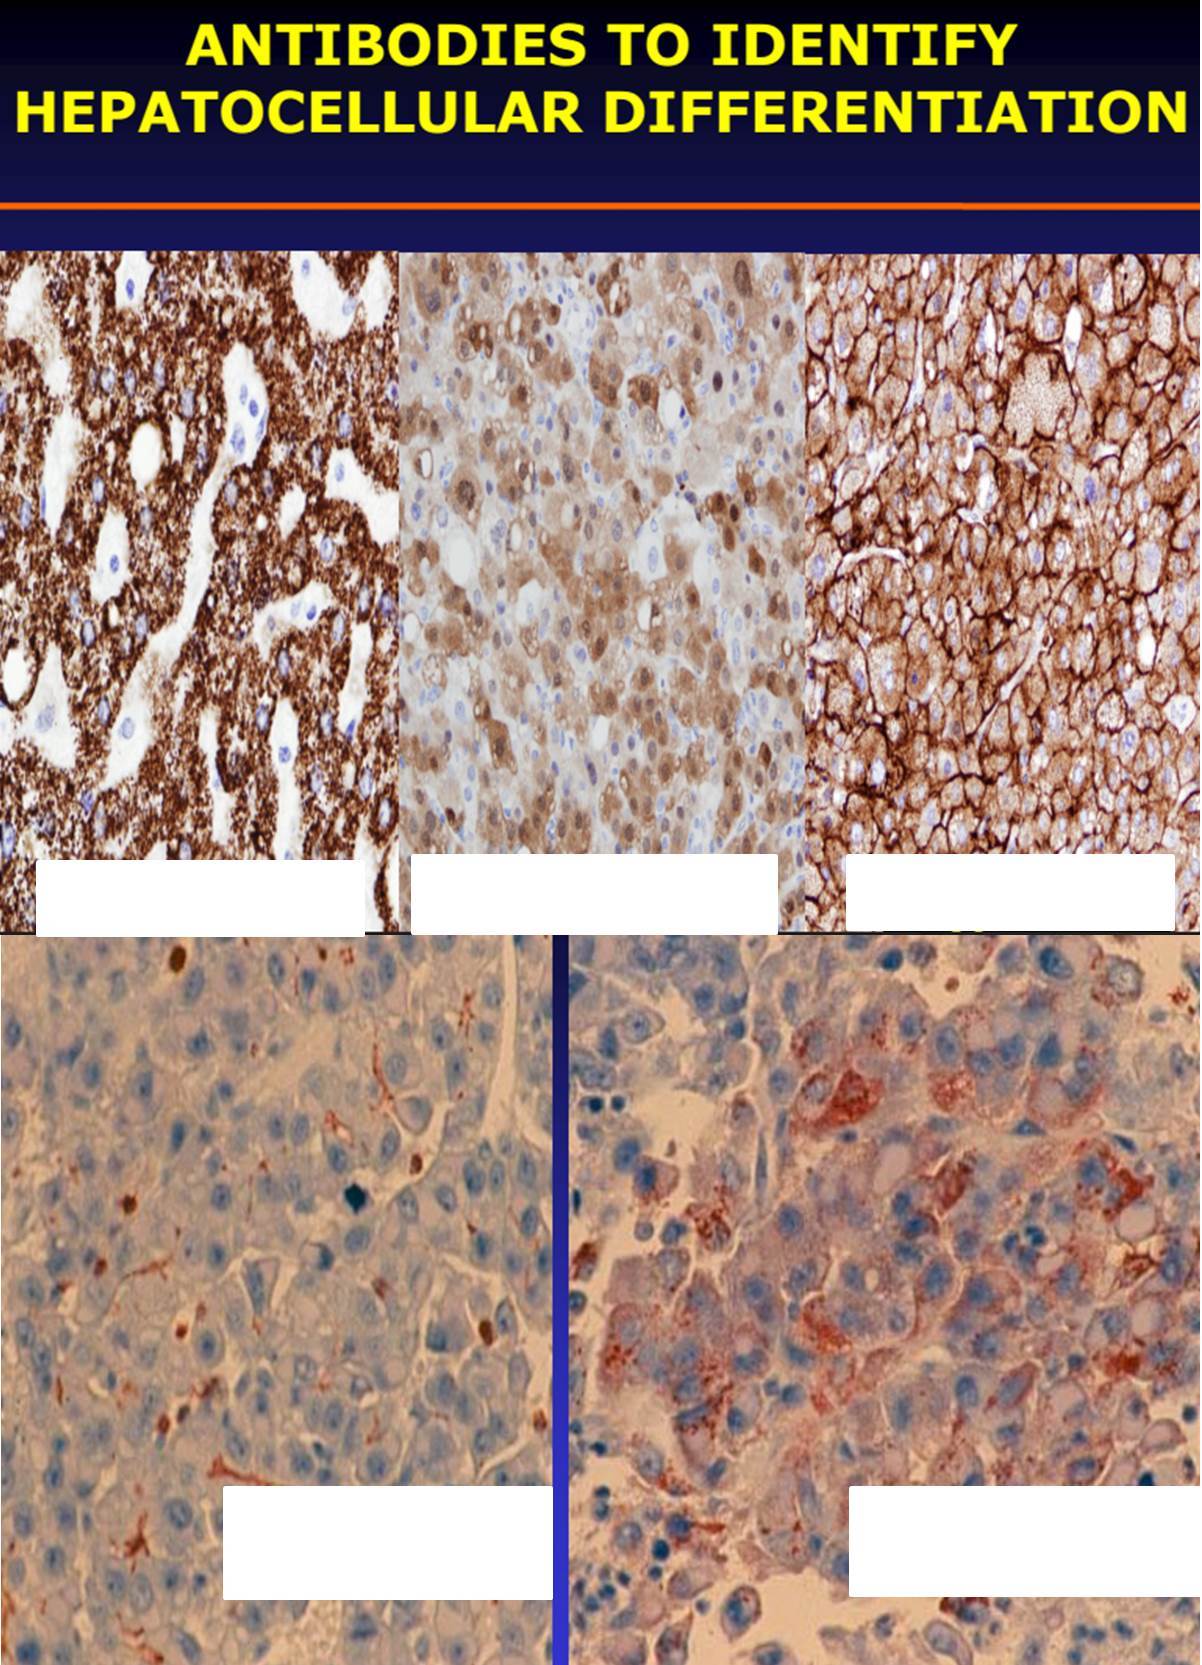

ANTIBODIES TO IDENTIFY

HEPATOCELLULAR DIFFERENTIATION